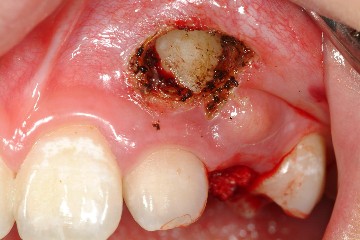

以下圖片分別為手術前、手術後情形

圖三 |